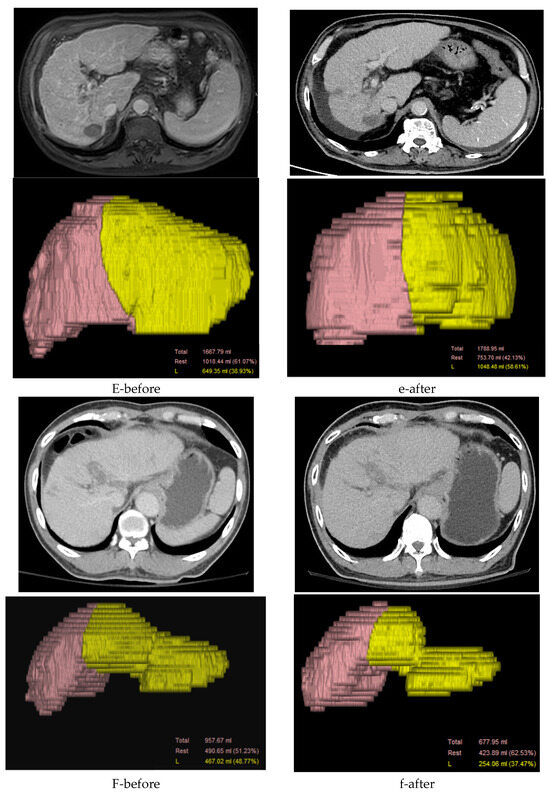

Imaging Features of Patients with Hepatocellular Carcinoma and Portal Vein Tumor Thrombosis Surviving Beyond 1 Year After Combined Therapy

Background/Objectives: Portal vein tumor thrombus (PVTT) is a severe complication of hepatocellular carcinoma (HCC) and is associated with poor outcomes. This study aimed to describe the imaging and clinical characteristics observed among HCC patients with PVTT who survived longer than one year following combined systemic therapy and radiotherapy. Methods: This retrospective, single-center study included 26 consecutive HCC patients with PVTT who survived more than one year after combined treatment. Baseline characteristics included PVTT extent classified according to the Liver Cancer Study Group of Japan—VP1 (segmental portal vein invasion), VP2 (second-order portal vein invasion), VP3 (first-order portal vein invasion), and VP4 (main portal trunk or contralateral PV invasion) and liver function assessed by Child–Pugh class and ALBI grade. Contrast-enhanced CT or MRI was evaluated at baseline and 6 months after treatment using RECIST 1.1 criteria. Results: The cohort was predominantly male (69%), and most patients had extensive PVTT (VP3–VP4, n = 19). Preserved liver function was common at baseline (Child–Pugh class A, n = 24; ALBI grade I, n = 14). Tumor response was observed in 23 patients (88%) during follow-up. Frequently observed post-treatment imaging findings included portal vein recanalization (n = 12), collateral circulation (present in 7 patients at baseline and 6 at follow-up), and compensatory liver hypertrophy (n = 6). Conclusions: Among HCC patients with PVTT who survived longer than one year after combined therapy, portal vein recanalization, collateral circulation, and compensatory liver hypertrophy were commonly observed imaging features. Given the retrospective design and survivor-selection nature of the study, these findings should be interpreted as descriptive observations rather than evidence of treatment efficacy or prognostic determinants. Full article

Show Figures

Figure 1